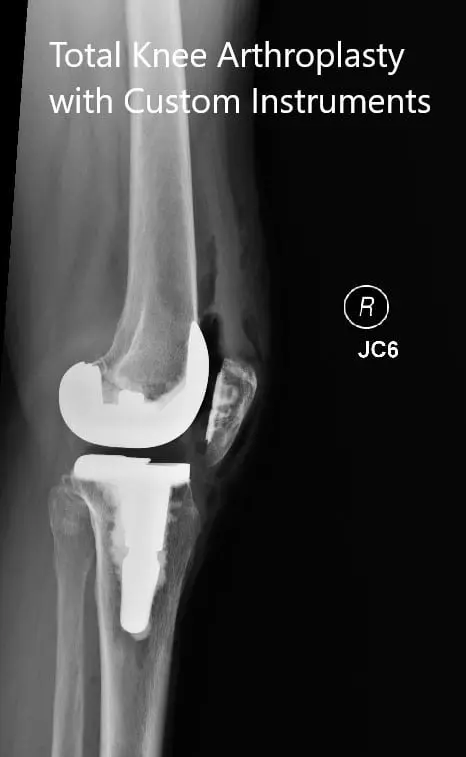

OPERATION: Right total knee replacement.

IMPLANTS USED: Femur posterior stabilized size 3 with a Persona tibia 5-degree stemmed size C with polyethylene 10-mm posterior stabilized insert with 14-mm diameter stem extension with 29-m cemented patella.

Postoperative x-rays showing the anteroposterior and lateral views of the right knee.